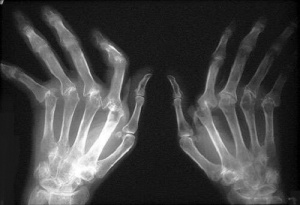

Reumatoïde artritis is een chronische progressieve gewrichtsaandoening. De ziekte ontstaat vanuit het gewrichtsvlies, dat gaat woekeren en zowel het kraakbeen als het omliggend bot aantast.

Vooral de kleinere gewrichten in de handen en de voeten worden getroffen. Het gewrichtskapsel raakt geleidelijk aan ontstoken en opgezwollen. Als de aandoening verder gaat, kunnen de botten die met het gewricht in verbinding staan, beschadigd worden en erosie vertonen.

Veel patiënten met reumatoïde artritis vertonen reumaknobbels in de buurt van de aangetaste gewrichten, waardoor de aandoening makkelijk herkenbaar is. Het zijn de typische onderhuidse hobbels op de handen en voeten of binnenin het lichaam. Na enkele maanden of jaren ontstaat vaak ook misvorming van de gewrichten.